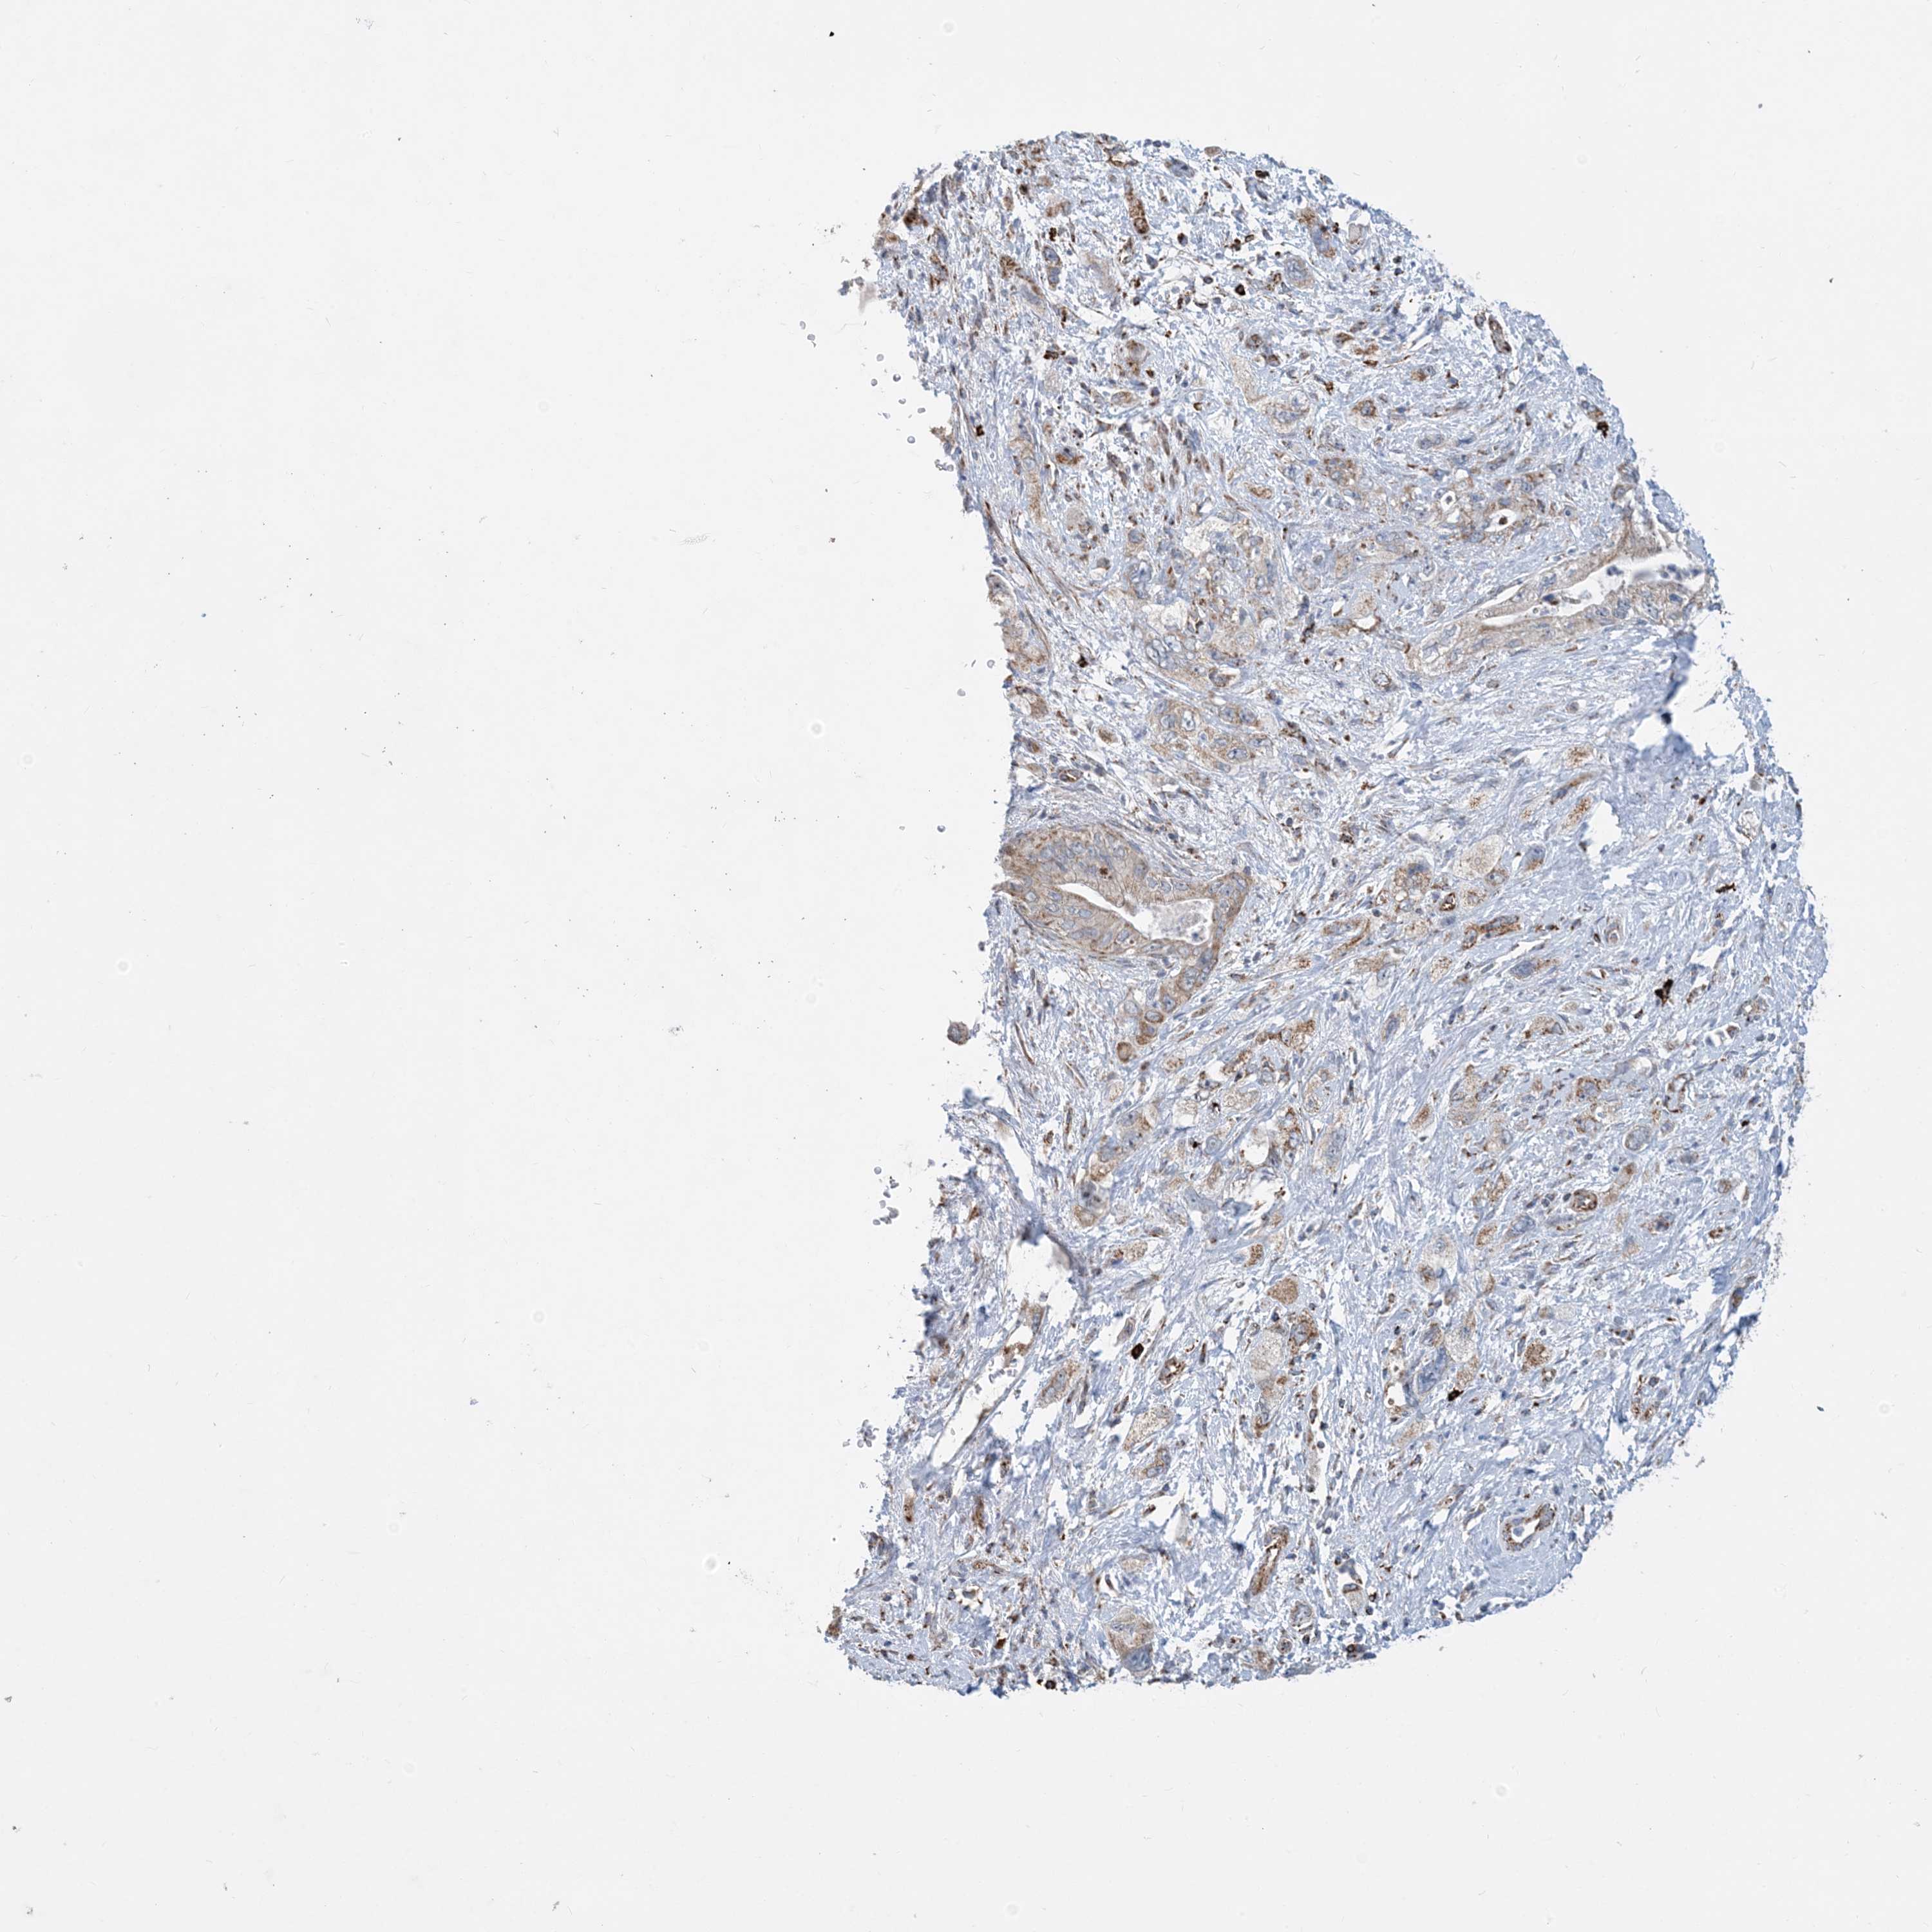

PANCREATIC CANCER - Protein expressioni

A mouse-over function shows sample information and annotation data. Click on an image to view it in a full screen mode. Samples can be filtered based on level of antibody staining by selecting one or several of the following categories: high, medium, low and not detected. The assay and annotation is described here.

Note that samples used for immunohistochemistry by the Human Protein Atlas do not correspond to samples in the TCGA dataset.

Antibody stainingi

Antibody staining in the annotated cell types in the current human tissue is reported as not detected, low, medium, or high, based on conventional immunohistochemistry profiling in selected tissues. This score is based on the combination of the staining intensity and fraction of stained cells.

Each image is clickable and will lead to virtual microscopy that enables deeper exploration of all samples and also displays staining intensity scores, fraction scores and subcellular localization as well as patient and tissue information for each sample.

Antibody HPA008755

Antibody HPA036547

Staining

High

Medium

Low

Not detected

Intensity

Strong

Moderate

Weak

Negative

Quantity

>75%

75%-25%

<25%

None

Adenocarcinoma, NOS